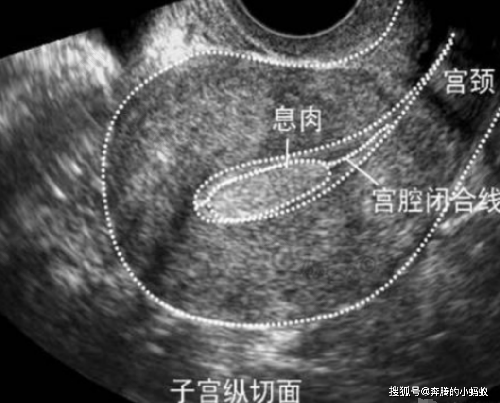

子宫息肉是女性比较常见的一种妇科疾病,虽然在日常生活中不会带来太大的影响,但是站在女性健康的角度来讲,还是及时治疗最为妥当。但是子宫息肉在治疗过后还会有复发的可能。那么,怎么抑制子宫息肉复发?

由于子宫息肉容易复发,在术后应密切观察息肉的状况,这就需要患者定期回到医院进行检查。为排除癌变可能,子宫息肉术后必须把息肉送去接受病理检查。